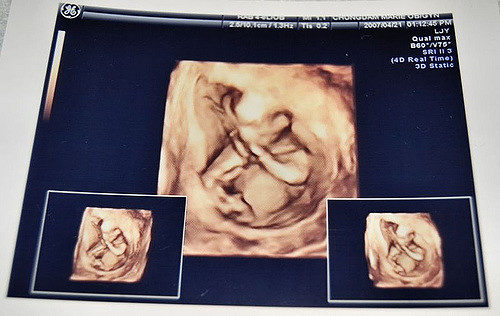

For expectant mothers, one of the most precious moments between them and their unborn child is getting to feel them kick for the first time.

Feeling your child kick is the first real sign that there’s an actual human growing inside and while at times it can be uncomfortable, it’s a moment most mothers will ignore the discomfort to experience. But unfortunately for one mother in China, her tiny tyke kicked a little too hard, leaving mom in a life-or-death situation.